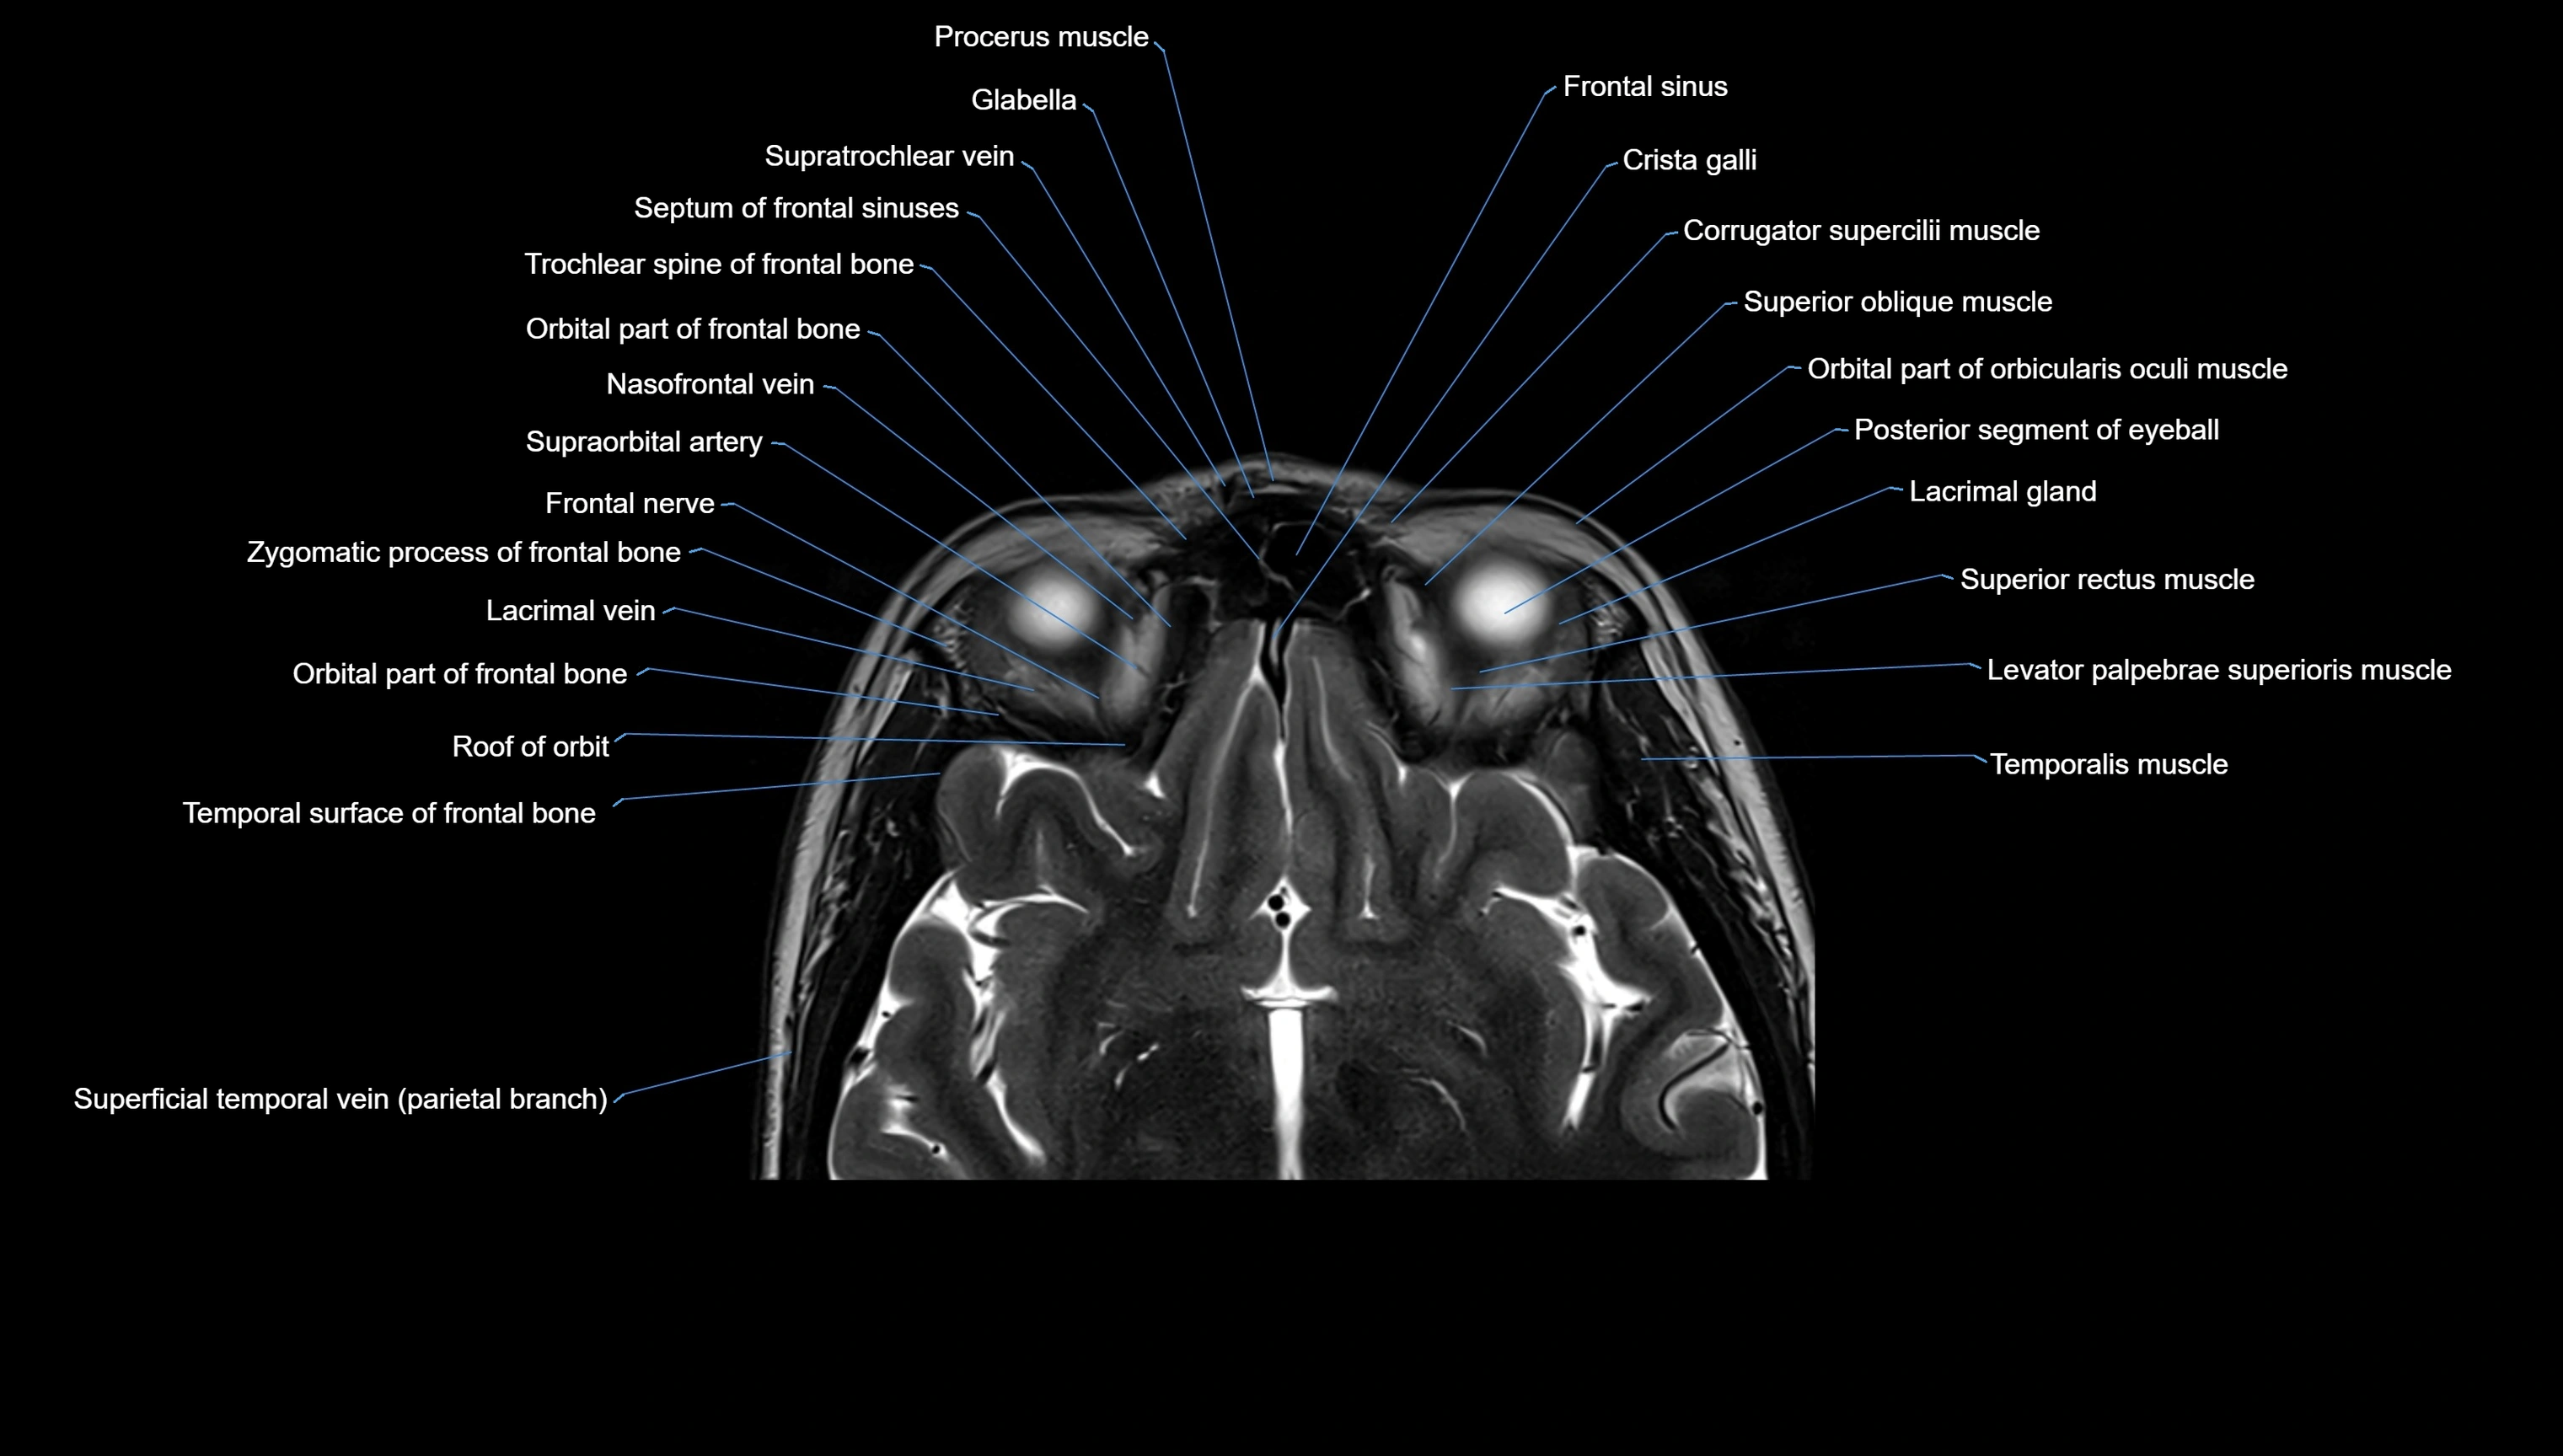

MRI images